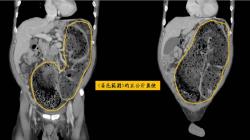

現代人常有便秘的困擾,若沒有太嚴重,通常不會太在意。不過有一項11萬人的研究證實,1周排便少於3次的人,大腦會老化3歲,記憶力變差的風險更超過7成,而排便後腦袋反而變清醒了。

蕭捷健分享2023年發表於《Neurology》醫學期刊一項追蹤超過11萬人的大型研究,1周排便少於3次的人,認知能力退化程度相當於大腦老了整整3歲,記憶力變差的風險也高出73%。